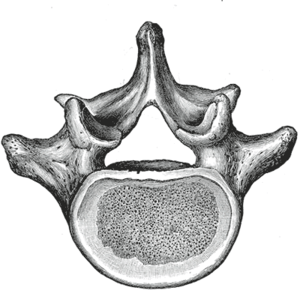

في التشريح البشري الفقرة القطنية Lumbar vertebrae، هي خمس فقرات تقع بين القفص الصدري والحوض. وهي أكبر قطاعات في العمود الفقري وتتميز بعدم وجود الثقبة المستعرضة داخل الحدبة العرضية (حيث أنها توجد فقط في المنطقة الرقبية)، وبعدم وجود الوجيهات على جانبي الجسم. وتسمى الفقرات القطنية حسب ترتيبها من أعلى ل1، ل2، ل3، ل4، ول5. الفقرات القطنية تساعد في دعم وزن الجسم، وتسمح بالحركة.

الخصائص العامة

صورة جانبية لفقرة قطنية